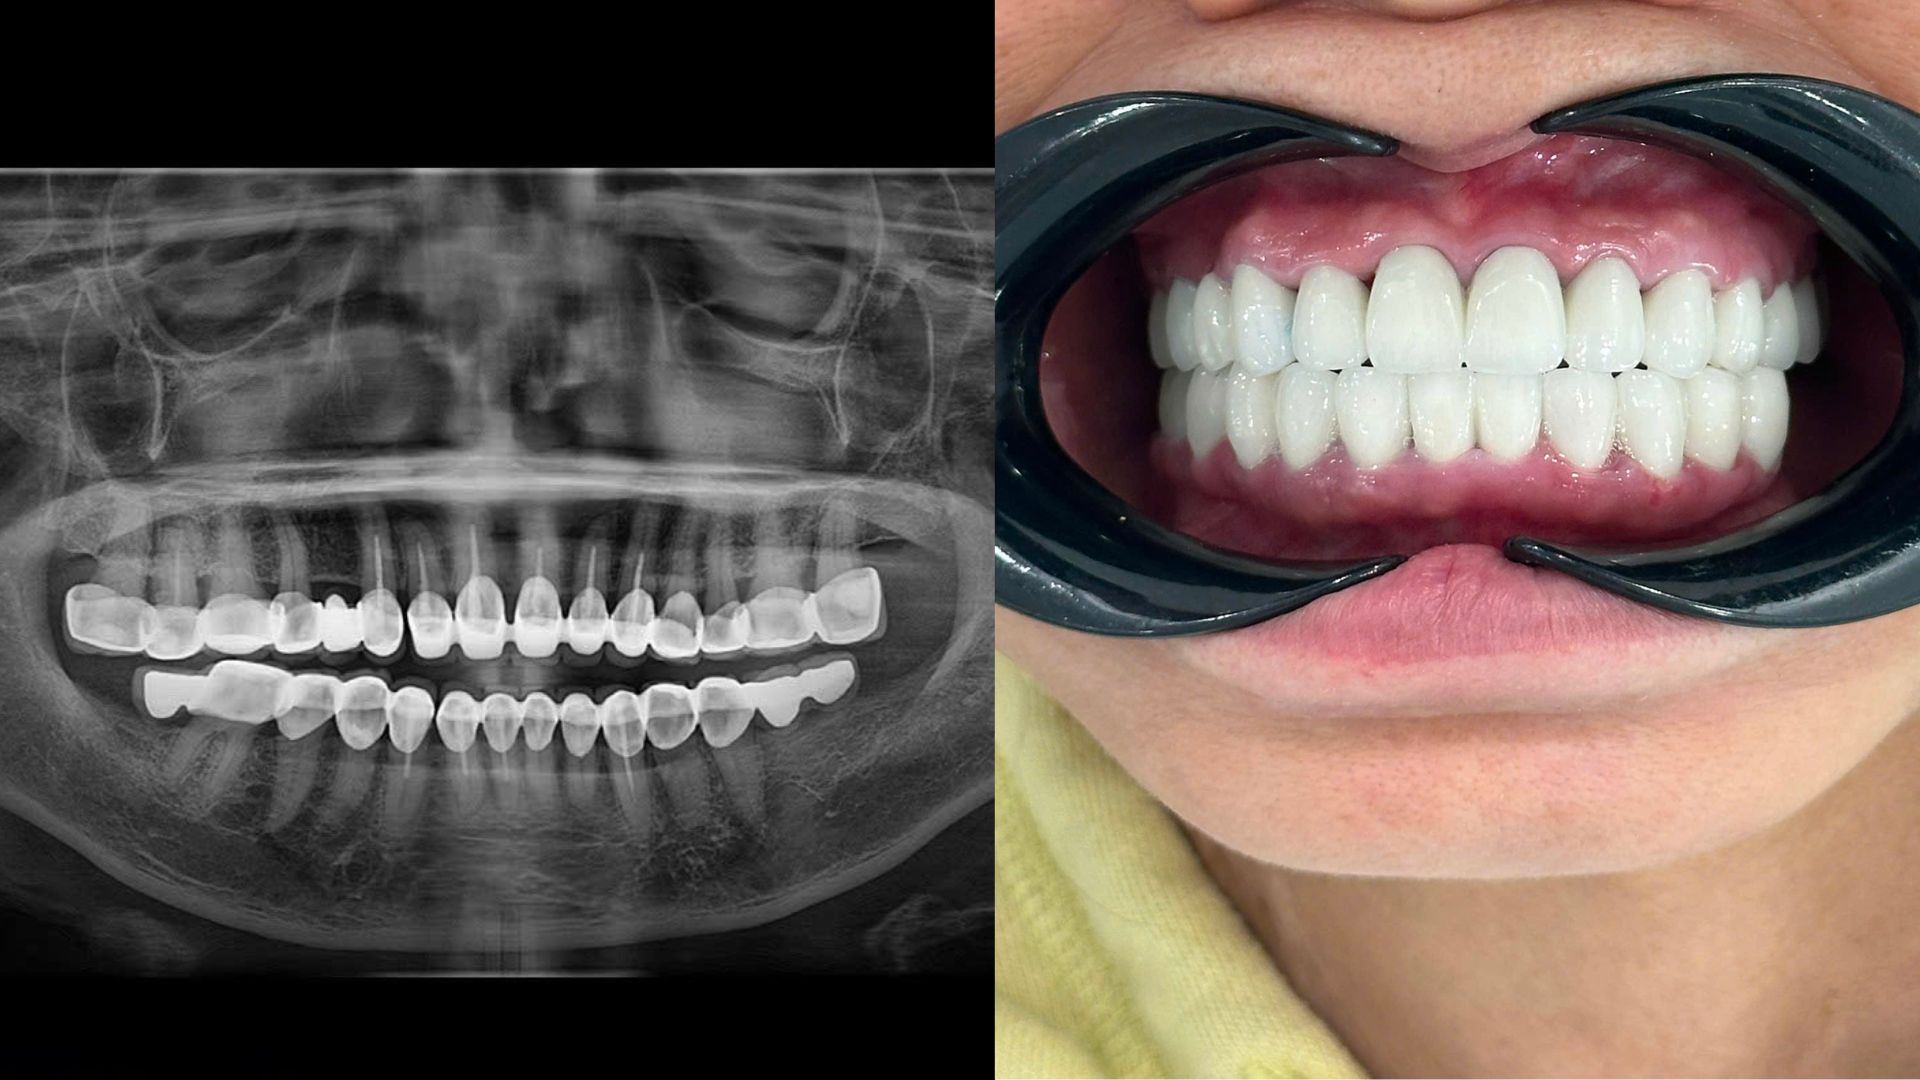

Qua thăm khám tổng quát và chụp X-quang, bác sĩ ghi nhận bệnh nhân đã bọc răng sứ toàn hàm trên và dưới, đồng thời từng lấy tủy 10 răng cửa. Tuy nhiên, dù đã lấy tủy nhưng nhiều răng vẫn còn đau nhức, ê buốt và có dấu hiệu viêm nhiễm quanh chân răng. Đặc biệt, phần răng sứ hàm dưới còn được làm cầu tại vị trí không có chân răng (3 cầu vói), các đường hoàn tất hở khiến thức ăn dễ mắc kẹt, gây hôi miệng nặng.

Trước tình trạng này, các bác sĩ tại Nha khoa Hạnh Phúc đã chỉ định cắt bỏ toàn bộ răng sứ cũ, điều trị tủy lại 10 răng bị viêm, làm mới cầu răng sứ ở những vị trí có chân răng chắc khỏe. Riêng vùng không có chân răng, bệnh nhân sẽ được chỉ định cắm Implant khi đủ điều kiện.

Sau khi hoàn tất quá trình điều trị, bệnh nhân đã hết đau nhức, không còn hôi miệng, ăn nhai tốt trở lại.